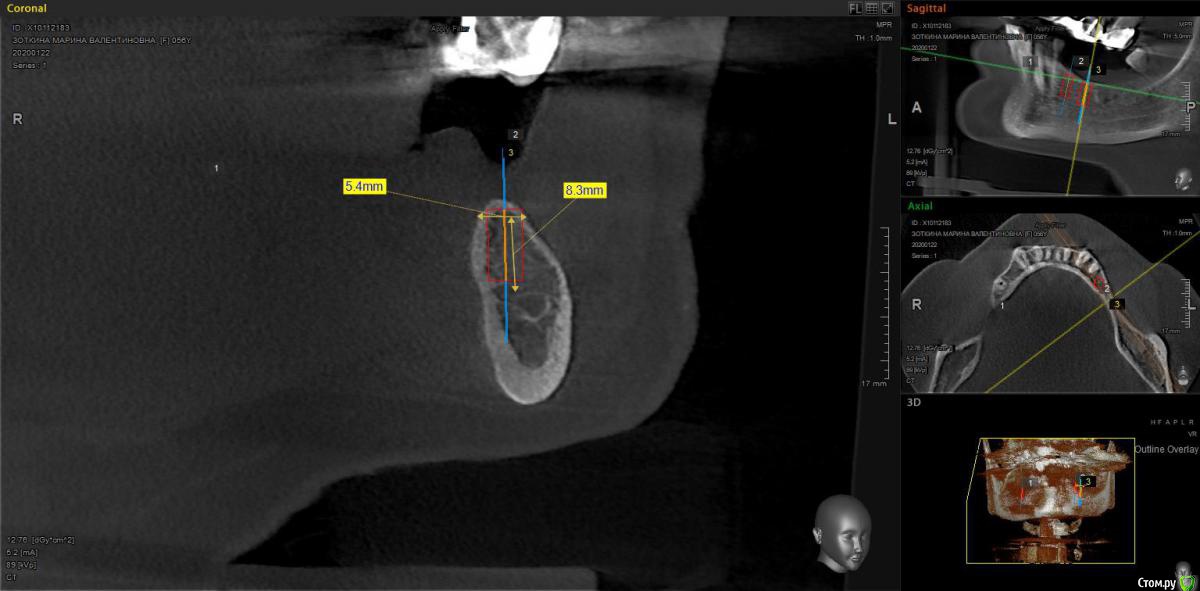

moises Опубликовано 16 февраля, 2020 Поделиться Опубликовано 16 февраля, 2020 Добрый день,коллеги.Планируется имплантация 34,36 и удаление 35, имплантация 45,46 удаление 48.1)Когда лучше убрать 35?одновременно с имплантацией,или допустимо убрать его за неделю-две до?2) 46 зуб- планирую провести НКР вестибулярно(ауто+ксено и резорбируемая мембрана ) и установить 4x8,5 или 4 x 7.3 Neibiotech.Возможности заглубить нет по причине близости нижнечелюстного канала,поэтому,как я понимаю придется установить крестально под заглушку.Тактика верная в этой ситуации? Ссылка на комментарий

moises Опубликовано 16 февраля, 2020 Автор Поделиться Опубликовано 16 февраля, 2020 1) не думаю, что есть какая-то разница, но одновременно будет комфортнее пациенту 2) если 4.6 это второй срез, а у Neobiotech конус, то 4х8 туда входит нормально, но не поскупитесь на стт вестибулярноКонус.То есть при ширине гребня 5,5(если считать в том месте,где планируется платформа) в боковом отделе рекомендуете ограничиться только мягкими тканями? Ссылка на комментарий

Irouil Опубликовано 16 февраля, 2020 Поделиться Опубликовано 16 февраля, 2020 Конус.То есть при ширине гребня 5,5(если считать в том месте,где планируется платформа) в боковом отделе рекомендуете ограничиться только мягкими тканями?Да. Ориентируйтесь на оральный край, там 1мм должен быть. Трансплантат обязательно сразу с винтом, независимо от времени установки ФДМ. 1 Ссылка на комментарий

krokomot Опубликовано 16 февраля, 2020 Поделиться Опубликовано 16 февраля, 2020 Второй имплантат можно установить под углом дистально, и впоследствии использовать мультиюнит, либо использовать 6 мм имплантат. 4.0 на мой взгляд тонковат для жевательного отдела. 1 Ссылка на комментарий